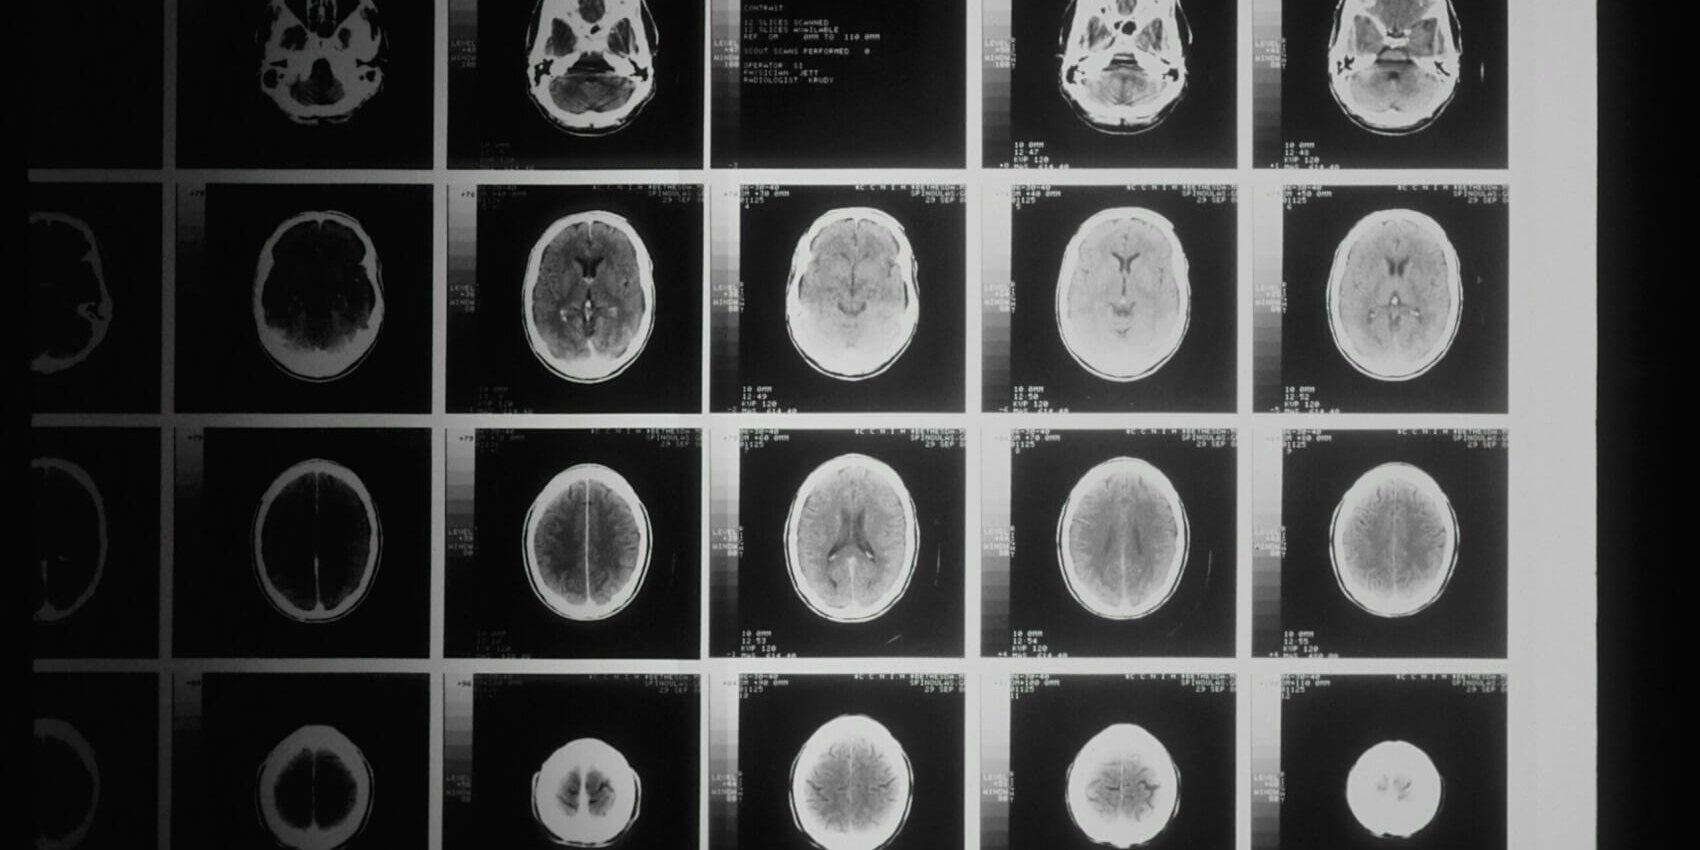

What is a Chiari Malformation?

A Chiari malformation is a problem in which a part of the brain (the cerebellum) at the back of the skull bulges through a normal opening in the skull where it joins the spinal canal. This puts pressure on parts of the brain and spinal cord, and can cause mild to severe symptoms. In most cases, the problem is present at birth (congenital).

There are several types of Chiari malformations, but type I is the most common. As mentioned above, in type I, the cerebellum bulges through the normal opening at the base of the skull. This type is most often congenital. It is also called primary Chiari malformation type I. But it is often not found until a person is a teen or young adult.